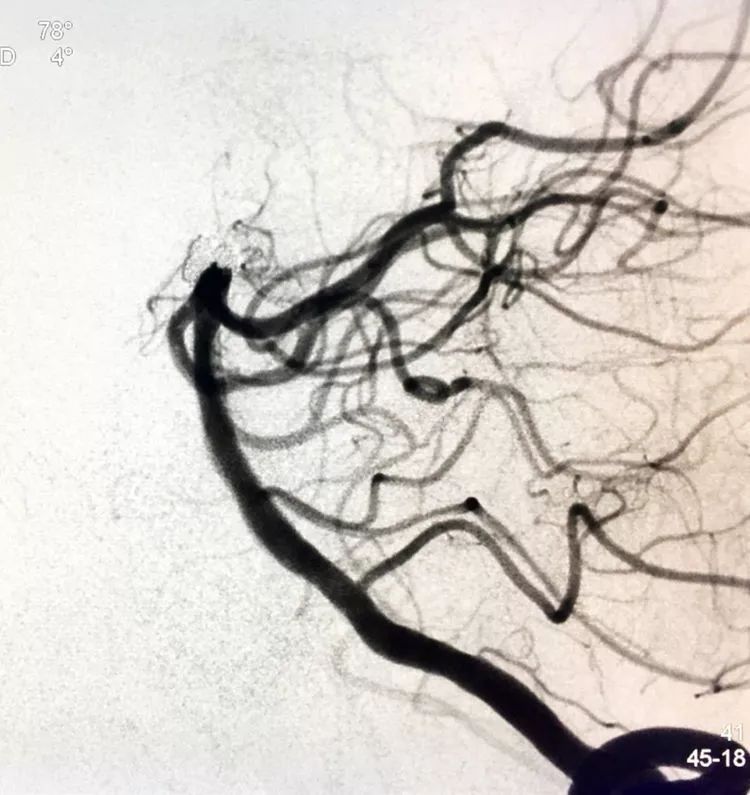

回到工作位造影,显示基底动脉顶端动脉瘤完全栓塞,基底动脉顶端四根血管畅通。

术后左椎动脉正位、侧位的造影和蒙片

挠痒挠个正着,舒服!